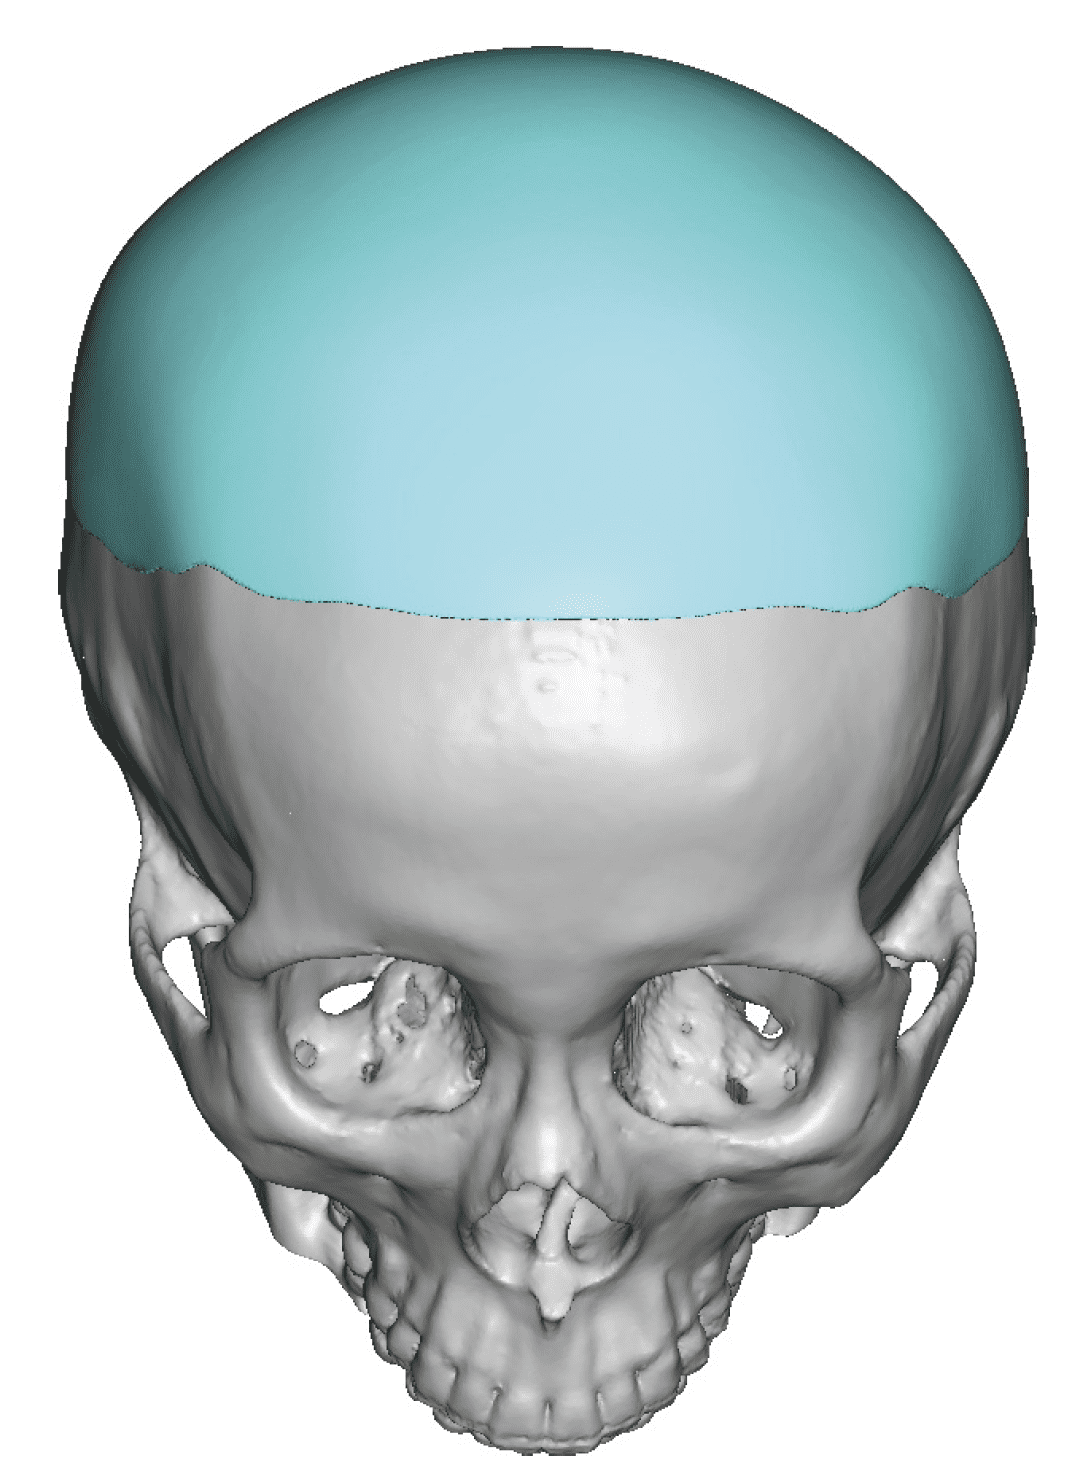

Patient 84

Desire for change of head shape from front view form an inverted V shape to a rounder and wider head shape.

Placement of custom extended forehead-temporal implants through incisions in the crease behind the ear. (he had a prior back of head skull implant which is green in the implant designs and which the head widening implants partially covered it)

Desire for change of head shape from front view form an inverted V shape to a rounder and wider head shape.

Placement of custom extended forehead-temporal implants through incisions in the crease behind the ear. (he had a prior back of head skull implant which is green in the implant designs and which the head widening implants partially covered it)